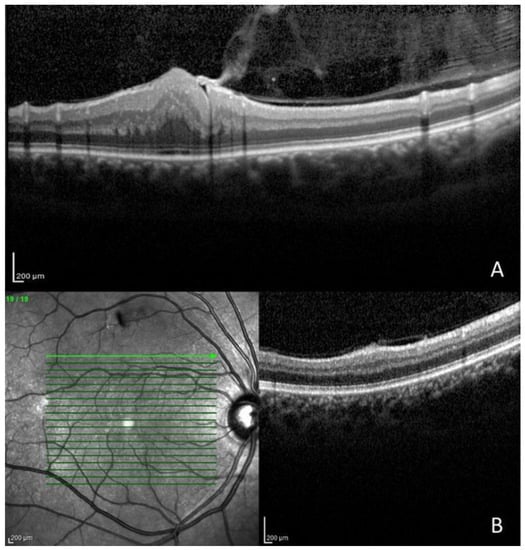

| 6 | F | 37 | 30 | 0.90 | 0.90 | Gardner variant | Cataract (RE), paramacular epiretinal membrane grade 2 and optic nerve edema (RE and LE), and exotropia |

| 14 | M | 16 | 10 | 1.00 | 0.03 | Wishart variant | Cataract (LE), epiretinal membrane grade 2 (RE and LE), and microstrabismus |

| Epiretinal membrane | 4 | 28.6% | 6 | 21.4% |